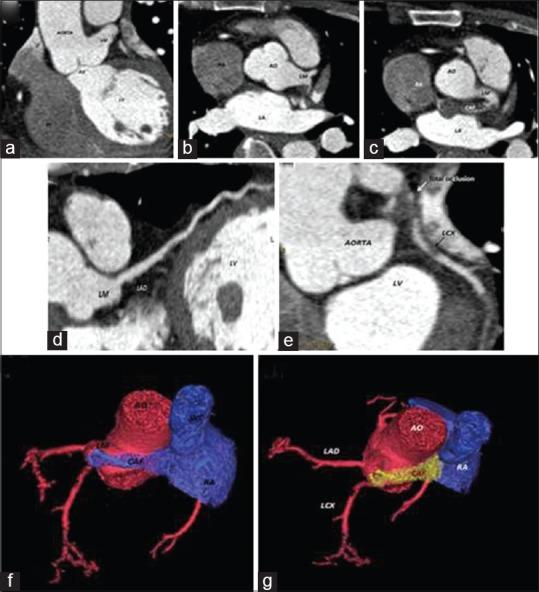

Coronary artery fistulas (CAFs): Are anomalous connections of the coronary arteries (CA) with major vascular structures or heart chambers. Most of CAFs are incidental findings during invasive coronary angiography (ICA) or computed tomography angiography (CTA). Many patients with CAFs are asymptomatic; only a minority has been associated with various clinical features and outcomes. We have reported a rare CAF complicated with acute myocardial infarction (AMI) in 43 years old female Patient who was admitted to our institution with a Diagnosis of Acute Infero-Posterior Myocardial Infarction (AMI). ICA and CTA showed a thrombosed CAF between left main coronary artery and right atrium with totally occluded left circumflex artery by a thrombus extended from the fistula. As there was a high risk associated with immediate intervention, the patient was kept on conservative management with a future plan of catheter-assisted or surgical closure. We have shown a rare case of CAF presenting with AMI that is unusual for such an anomaly, and have highlighted the role of CTA in the diagnosis and management of such rare disorder.

冠状动脉瘘(CAFs):是冠状动脉(CA)与主要血管结构或心腔的异常连接。大多数冠状动脉瘘是在有创冠状动脉造影(ICA)或计算机断层血管造影(CTA)期间偶然发现的。许多患有冠状动脉瘘的患者没有症状;只有少数患者与各种临床特征和预后相关。我们报道了一例罕见的冠状动脉瘘合并急性心肌梗死(AMI)的病例,该43岁女性患者因急性下后壁心肌梗死(AMI)诊断入院。ICA和CTA显示左冠状动脉主干与右心房之间有一个血栓形成的冠状动脉瘘,左旋支动脉被从瘘管延伸而来的血栓完全阻塞。由于立即干预存在高风险,患者接受保守治疗,并计划未来进行导管辅助或手术闭合。我们展示了一例罕见的以急性心肌梗死为表现的冠状动脉瘘病例,这种异常情况并不常见,并强调了CTA在诊断和管理这种罕见疾病中的作用。